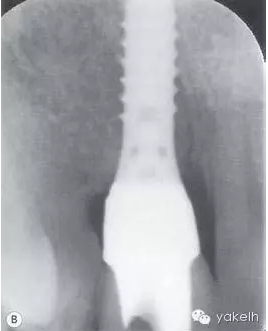

此病例中UR1發(fā)生種植體周圍炎,導(dǎo)致嚴(yán)重的美學(xué)問題。種植體周圍黏膜退縮,種植體頸部金屬暴露(圖.10A)。種植體唇側(cè)組織感染、腫脹,存在深牙周袋。影像學(xué)檢查顯示種植體周圍大面積骨喪失(圖.10B)。

圖.10 種植體植入位置不恰當(dāng),導(dǎo)致種植體周圍炎。